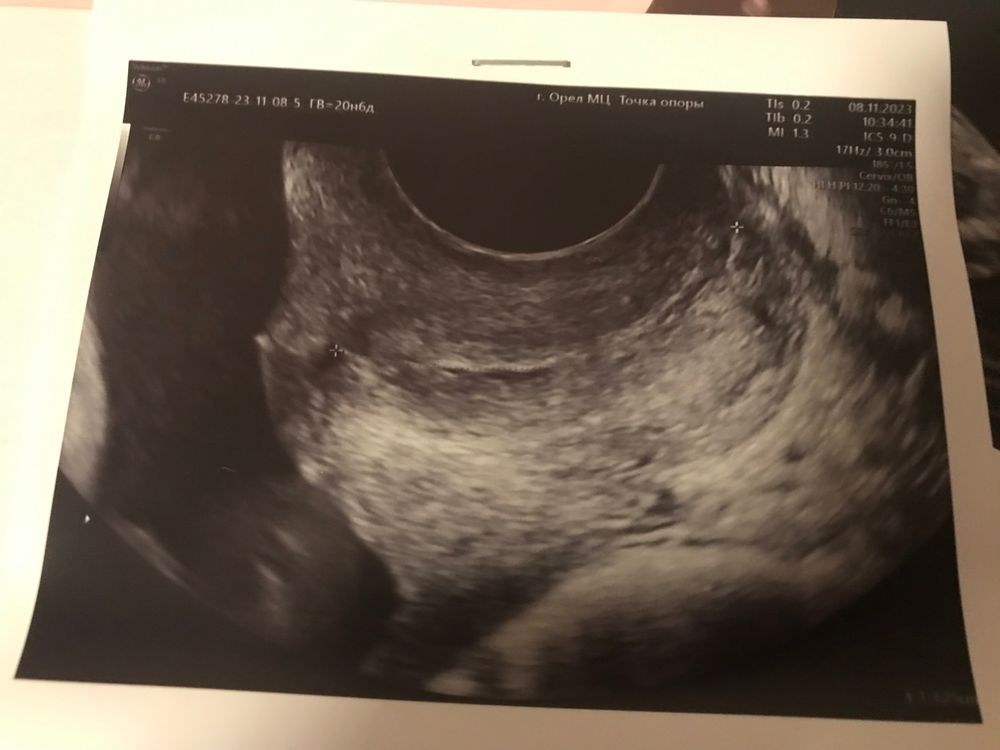

Шейка в 20 недель.

Здравствуйте девочки. Была сегодня на 2 скрине. По плоду 20 недель. Шейку намерили 32,5мм, внутренний зев закрыт. На первом скрине была 39мм. Сказали перемерить через 2 недели. Немного переживаю, я же плюс на утрике еше…почему укоротилась? Девочки, стоит ли переживать? Па с мужем не прекращали, и врач вроде не говорила воздерживаться. У кого было? Доходили без швов и песариев?